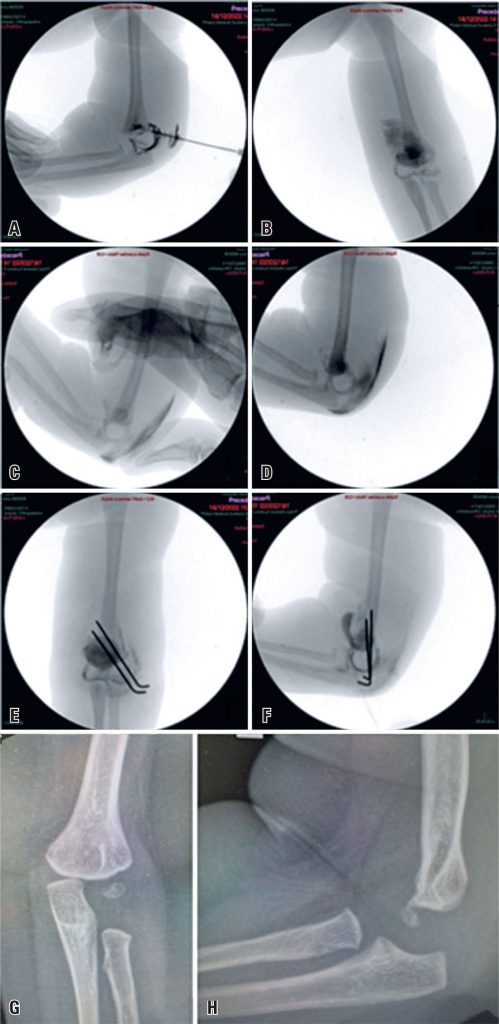

Epiphyseal displacement of the distal humerus is rare and difficult to diagnose. In addition, the literature on the prognosis and treatment is limited. Here, we present a case of distal humeral physeal separation with significant displacement in a neonate. A favorable outcome was obtained following closed reduction and percutaneous fixation with Kirschner wires assisted by arthrography. This report adds valuable information on this subject to the existing literature.